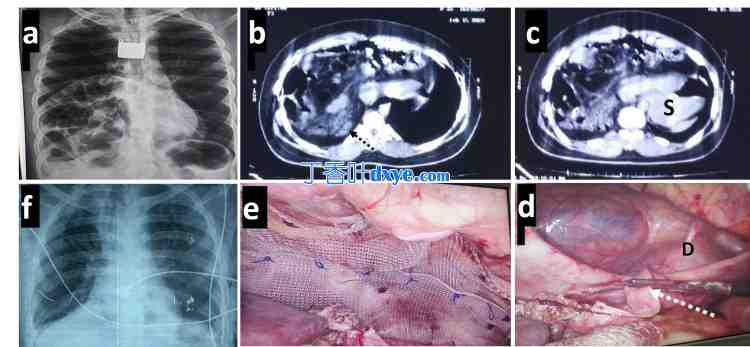

从左上角开始顺时针方向:(a) 术前胸片,右半胸腔内有多个内脏。(b) 横截面对比 CT 提示右胸腔血胸内有多个内脏,线性高密度(用虚线黑色箭头标记)可能代表萎缩的左肝。(c) 类似的 CT 图像显示胃(标记为 S)通过缺损进入胸腔并向左下垂。(d) 手术图像,大缺损(D)腹侧边缘不清晰。通过解剖萎缩的左肝(用虚线白色箭头标记)清除背侧边缘。(e) 缺损闭合,并放置了一个大的重叠网片。(f) 术后胸片,第七天肺完全扩张。